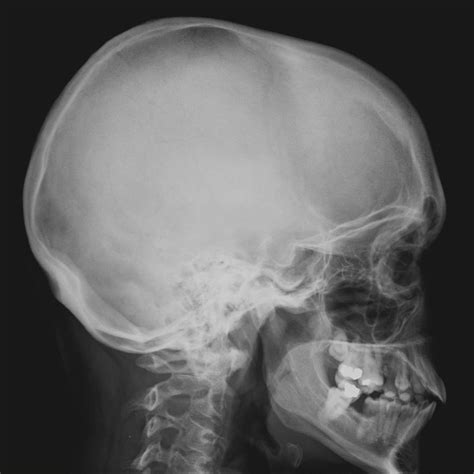

Understanding the anatomy of the skull is crucial for various fields, including medicine, forensics, and anthropology. One of the most informative views of the skull is the Skull Lateral View Labeled. This view provides a comprehensive look at the lateral aspects of the skull, revealing key structures and landmarks that are essential for identification, diagnosis, and research.

The lateral view of the skull reveals several key structures that are essential for understanding its anatomy. These structures include:

• Frontal Bone: The frontal bone forms the forehead and the roof of the eye sockets.

• Temporal Bone: The temporal bone is located on the sides of the skull and contains the structures of the ear.

• Parietal Bone: The parietal bones form the sides and roof of the cranium.

• Occipital Bone: The occipital bone is located at the back and base of the skull.

• Zygomatic Bone: The zygomatic bones form the cheekbones.

• Mandible: The mandible is the lower jawbone.

The Skull Lateral View Labeled also highlights several important anatomical landmarks. These landmarks are crucial for identifying specific regions of the skull and understanding its overall structure. Some of the key landmarks include:

• Glabella: The most prominent point on the frontal bone, located between the eyebrows.

• Nasion: The point where the frontal bone meets the nasal bones.

• Pterion: The point where the frontal, parietal, temporal, and sphenoid bones meet.

• Mastoid Process: A prominent bony projection on the temporal bone, located behind the ear.

• External Auditory Meatus: The opening of the ear canal.

• Zygomatic Arch: The bony arch formed by the zygomatic bone and the temporal bone.

The Skull Lateral View Labeled has numerous clinical applications. In medicine, this view is used to diagnose and treat various conditions affecting the skull and brain. For example, it can help identify fractures, tumors, and other abnormalities. In forensic analysis, the lateral view is used to identify individuals based on skull characteristics and to reconstruct facial features. In anthropology, it provides insights into the evolution and diversity of human skulls.